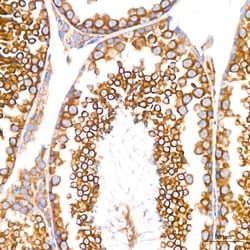

Invitrogen™ GRP94 Recombinant Rabbit Monoclonal Antibody (7P4V7)

| Applications | ELISA, Immunohistochemistry (Paraffin), Western Blot |

Immunogen sequence: EPLLNWMKDK ALKDKIEKAV VSQRLTESPC ALVASQYGWS GNMERIMKAQ AYQTGKDIST NYYASQKKTF EINPRHPLIR DMLRRIKEDE DDKTVLDLAV.

GRP94 is a 803 amino acid protein belonging to the heat shock protein 90 family. It acts as a molecular chaperone that functions in the processing and transport of secreted proteins. GRP94 and its N-terminal fragment stimulates CTL expansion and maturation of human monocyte-derived dendritic cells (MDDC). It plays a central role in innate as well as acquired immunity, maturation and chemotaxis of dendritic cells, Ab production, cross-priming, as a potential marker in breast cancer and is a peptide acceptor in endoplasmic reticulum and an accessory to peptide loading of MHC class I molecules. Expression of GRP94 suppressed A23187-induced apoptosis and stabilized calcium homeostasis. GRP94 is expressed in melanoma or liver metastases of colon carcinoma cells, human gastric carcinoma BGC-823 cells.Specifications

| ELISA, Immunohistochemistry (Paraffin), Western Blot | |

| A synthetic peptide corresponding to a sequence within amino acids 616-715 of human HSP90B1 (NP_003290.1). | |

| Human, Mouse, Rat | |